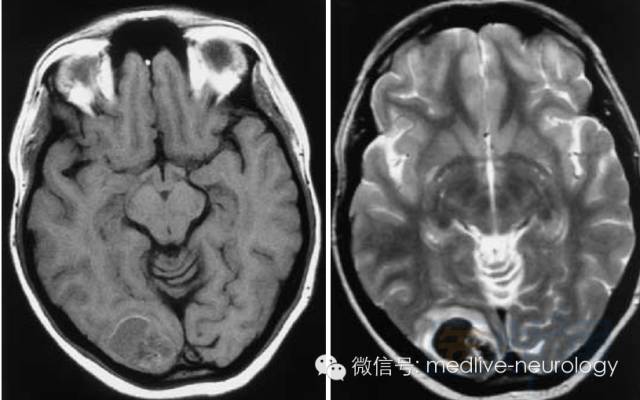

然后解决第三个问题,轻松一下,图来啦,让我们巩固一下今天学习的成果,均为先T1,后T2。

急性期(1-3d):右枕叶

亚急性早期(3-7d): 脑桥